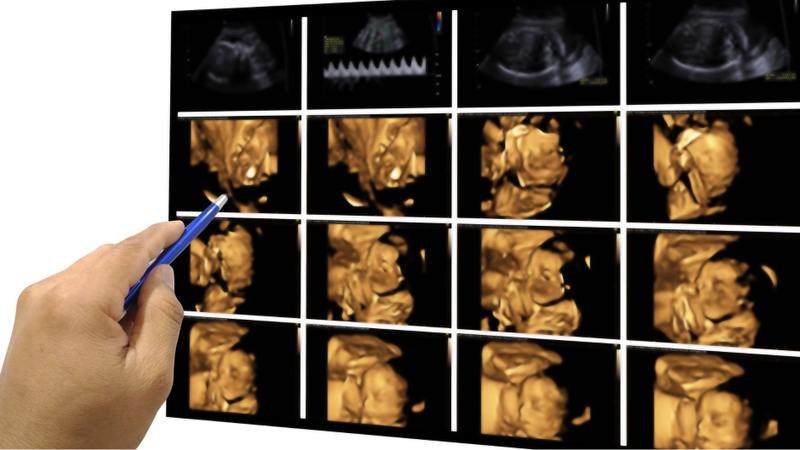

Siêu âm 4 chiều, còn được gọi là siêu âm 4D, là phương pháp chẩn đoán hình ảnh hiện đại cho phép thai phụ quan sát rõ ràng hình ảnh cũng như các cử động của thai nhi trong tử cung. Nhờ kỹ thuật này, bác sĩ có thể đánh giá chính xác hơn quá trình phát triển và tình trạng sức khỏe của thai nhi.

Siêu âm 2D là kỹ thuật truyền thống, được ứng dụng từ rất sớm. Nhờ sự phát triển không ngừng của khoa học công nghệ, ngày nay đã xuất hiện thêm siêu âm 3D và 4D, mang đến hình ảnh rõ nét và sinh động hơn so với siêu âm 2D vốn chỉ hiển thị hình ảnh đen trắng như phim chụp. Siêu âm 4D được nâng cấp từ công nghệ 3D, không chỉ tái hiện hình ảnh không gian ba chiều mà còn ghi lại các chuyển động của thai nhi theo thời gian thực. Nhờ đó, bác sĩ và cha mẹ có thể quan sát hình dáng, cấu trúc cũng như cử chỉ của bé một cách chân thực và rõ ràng hơn.

Siêu âm 4D mang lại hình ảnh sắc nét, sống động, giúp gia đình có thể lưu giữ lại những khoảnh khắc bé cử động trong bụng mẹ như một kỷ niệm ý nghĩa. Đây được xem là ưu điểm nổi bật của siêu âm 4D so với các phương pháp siêu âm trước đây, bởi ngay cả sau này khi xem lại, cha mẹ vẫn có thể cảm nhận được những cảm xúc thiêng liêng trong giai đoạn mang thai. Bên cạnh đó, các thông số và chỉ số của thai nhi vẫn được hiển thị đầy đủ, hỗ trợ bác sĩ phát hiện sớm và chính xác các dị tật bẩm sinh ở trẻ.

Bên cạnh giá trị y học, siêu âm 4D còn mang đến ý nghĩa tinh thần to lớn cho gia đình. Việc được tận mắt nhìn thấy con yêu khi các bộ phận đã phát triển hoàn chỉnh giúp cha mẹ có những khoảnh khắc đầy cảm xúc. Những cử động đầu đời như mỉm cười, đạp chân hay mút tay của bé được ghi lại sinh động, tạo nên sự gắn kết thiêng liêng giữa cha mẹ và con ngay từ khi bé còn trong bụng mẹ.

Giai đoạn tam cá nguyệt thứ hai và tam cá nguyệt cuối được xem là thời điểm phù hợp để mẹ bầu thực hiện siêu âm thai 4D, thường bắt đầu từ khoảng tuần thai 20-24. Lúc này, các cơ quan và bộ phận trên cơ thể thai nhi đã phát triển tương đối hoàn chỉnh, nhờ đó hình ảnh thu được sẽ rõ nét hơn, giúp mẹ dễ dàng quan sát đặc điểm hình thể của con.